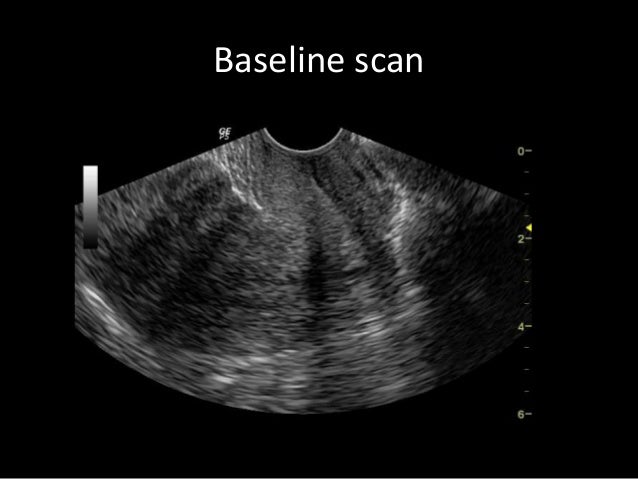

Ultrasound in early pregnancy (before 12 weeks) - Dating Scan Dating ultrasound A 'dating ultrasound' or 'dating scan' is a scan done early in pregnancy (before 12 weeks) . It is usually done to check how many weeks pregnant you are and therefore to calculate the estimated due date, but it can be done for other reasons . Only a few women need a dating scan .

Sometimes a TVS is also done to date your pregnancy to be sure your due date is correct . After 10 weeks and for the rest of your pregnancy, you will have abdominal scans because once your uterus expands and moves up in your abdomen, your baby becomes more visible through your tummy .